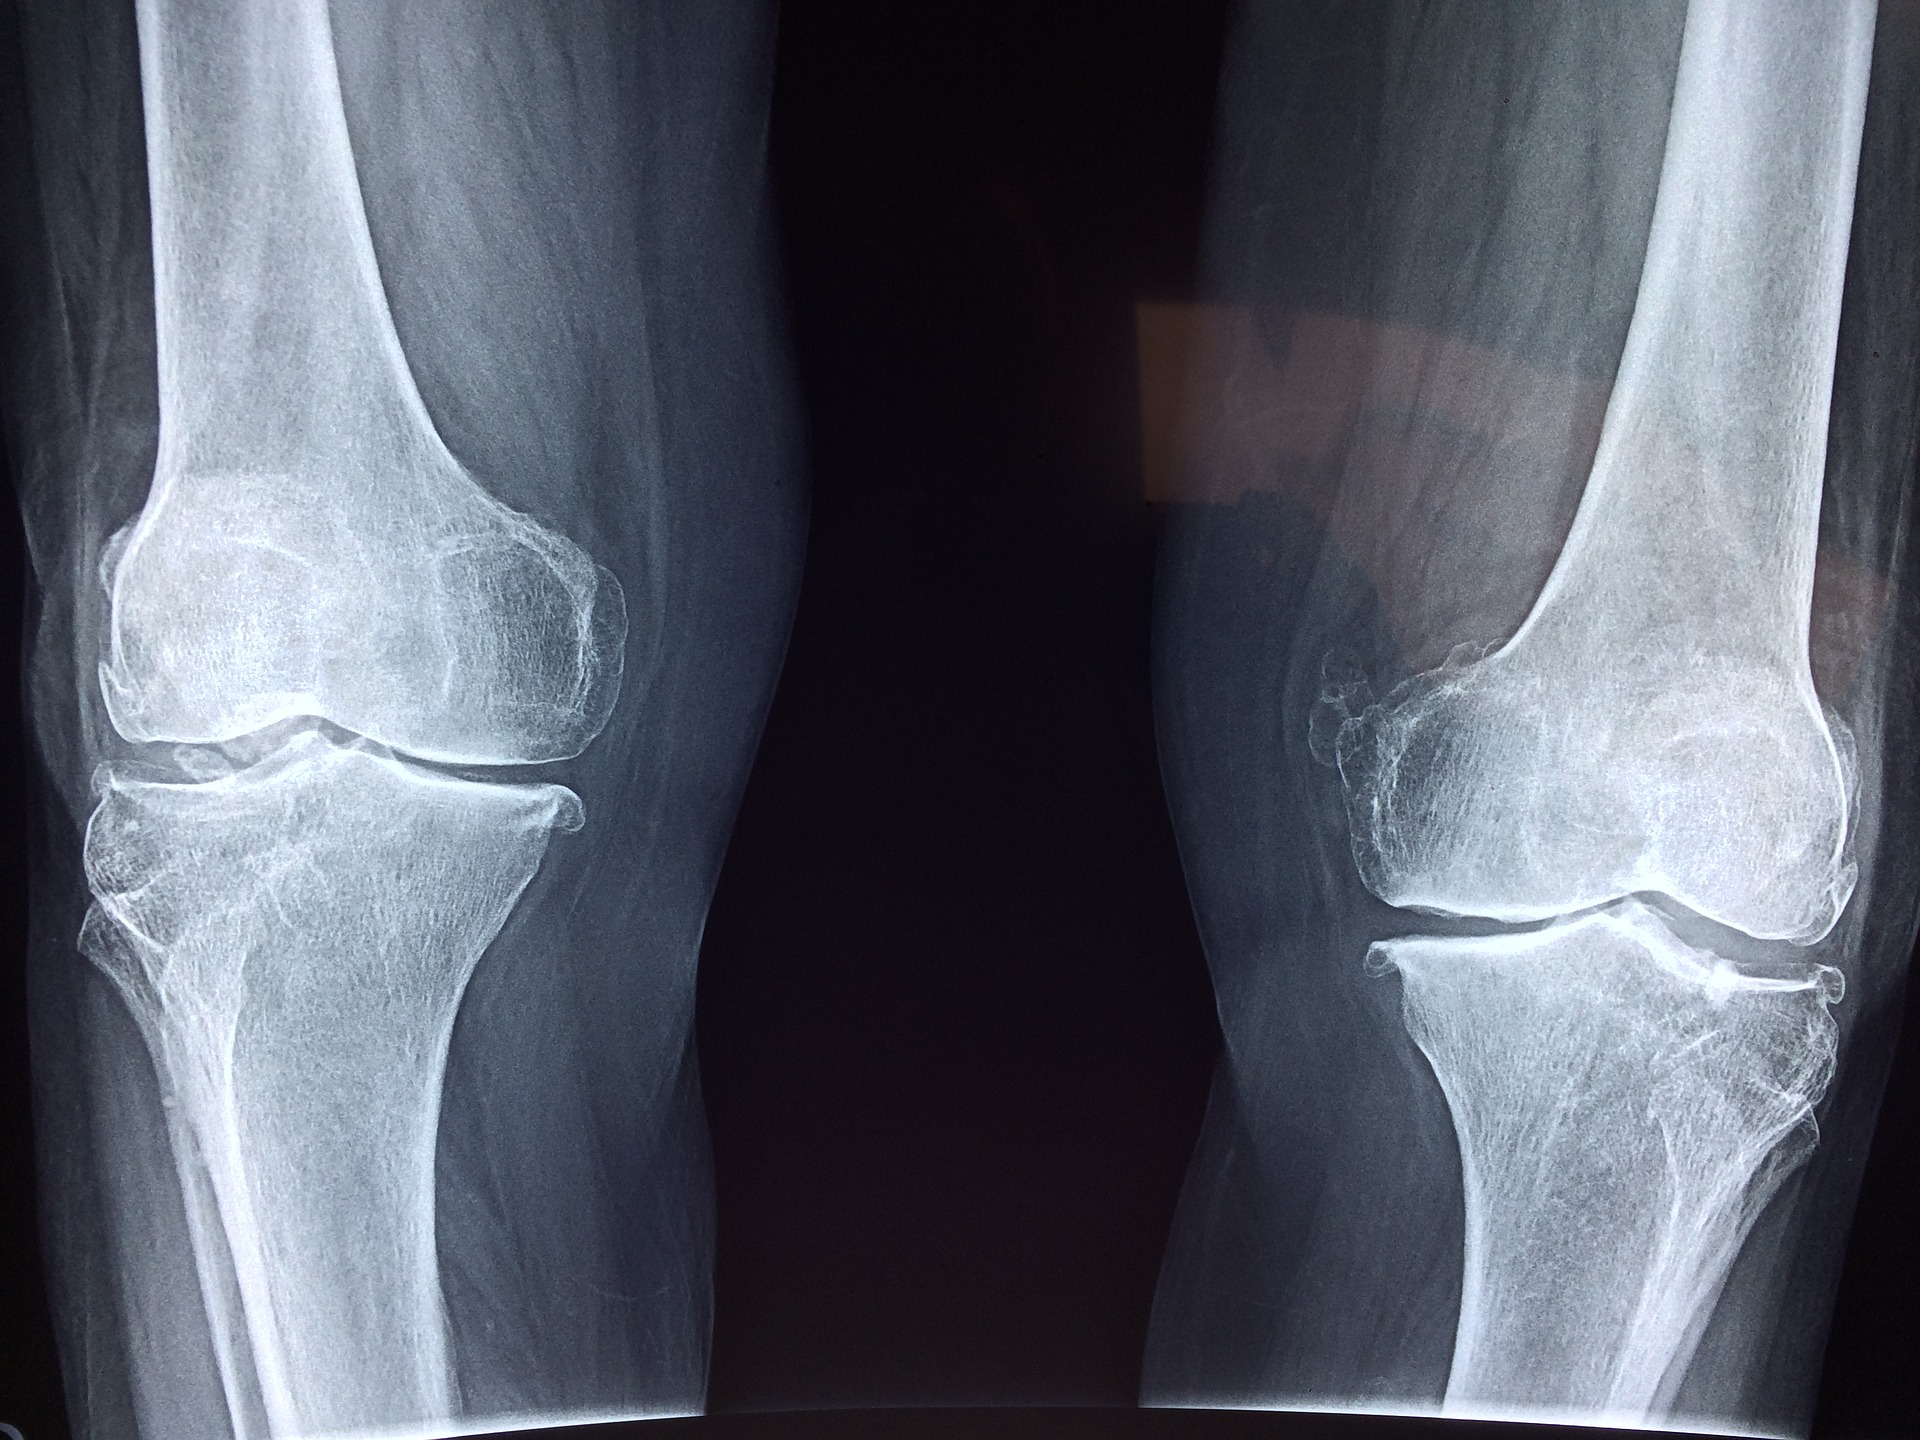

Wszelkiego rodzaju uszkodzenia ścięgien są bardzo wielkim problemem. Zdarza się to nie tylko sportowcom, ale …